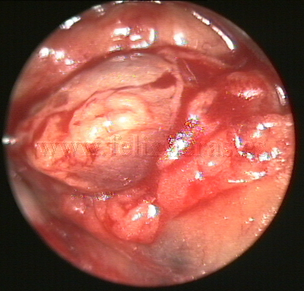

Adenopatías mediastínicas. Linfoma.

Videomediastinoscopia